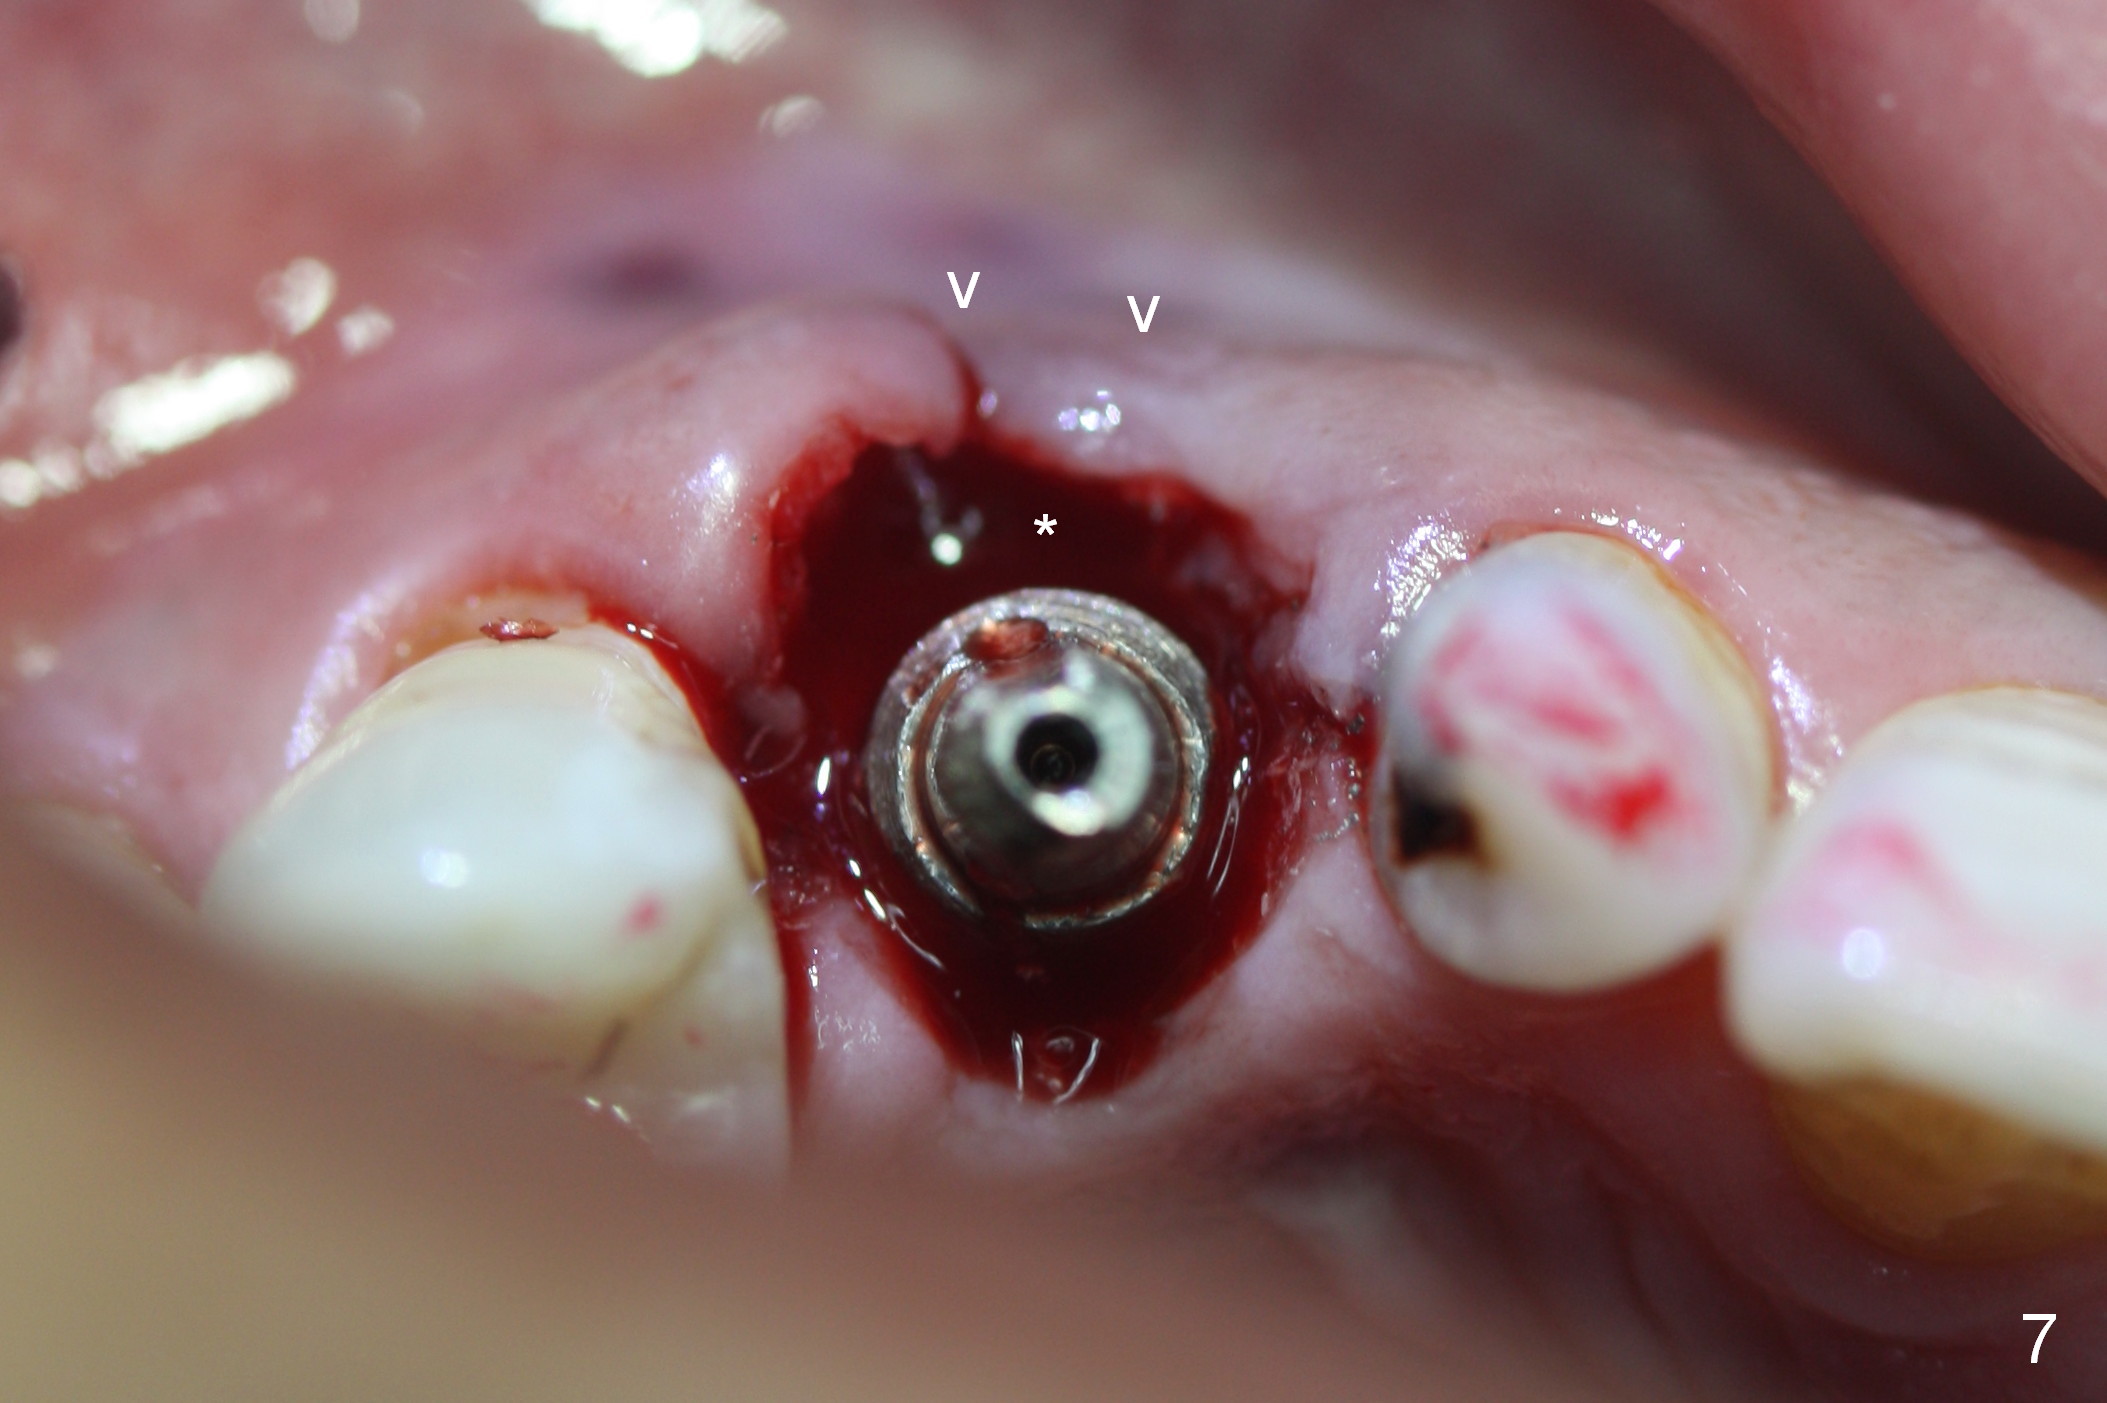

After 5x20 mm implant is placed, the distal gap is filled with bone graft (Fig.5 *). An abutment is placed (A) for fabrication of an immediate provisional (Fig.6 P). The latter hold the labial gingiva bulging (Fig.6 >). When the provisional is removed for bone grafting, the labial gingiva collapses (Fig.7 arrowheads). In fact a piece of cone-shaped Osteotape (Impladent) is placed palatal to the labial gingiva/thin labial plate and a small amount of graft is placed in the deepest area of the socket (labial to the osteotomy) prior to placement of the implant. More graft is placed in the peri-implant gap, particularly labially to keep the labial gingiva convex (Fig.8 arrowheads). The lacerated gingiva is to be approximated with perio glue (Fig.9 <). Collagen dressing is placed over the exposed graft before cementation of the provisional. Perio dressing is applied for further protection and seal.